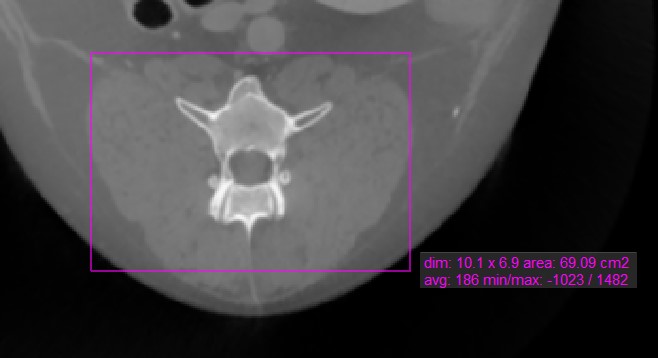

Rectangle¶

Select the Rectangle

tool and assign it to one of the available mouse buttons. Start the measurement by pressing on the active image slice and drag the mouse to obtain a rectangular shape. Release the mouse

when satisfied with the size of the marked area.

All available measurement values are displayed alongside the measurement.

Modify the marked area by moving one of the four points of the rectangular shape using the Default

tool.